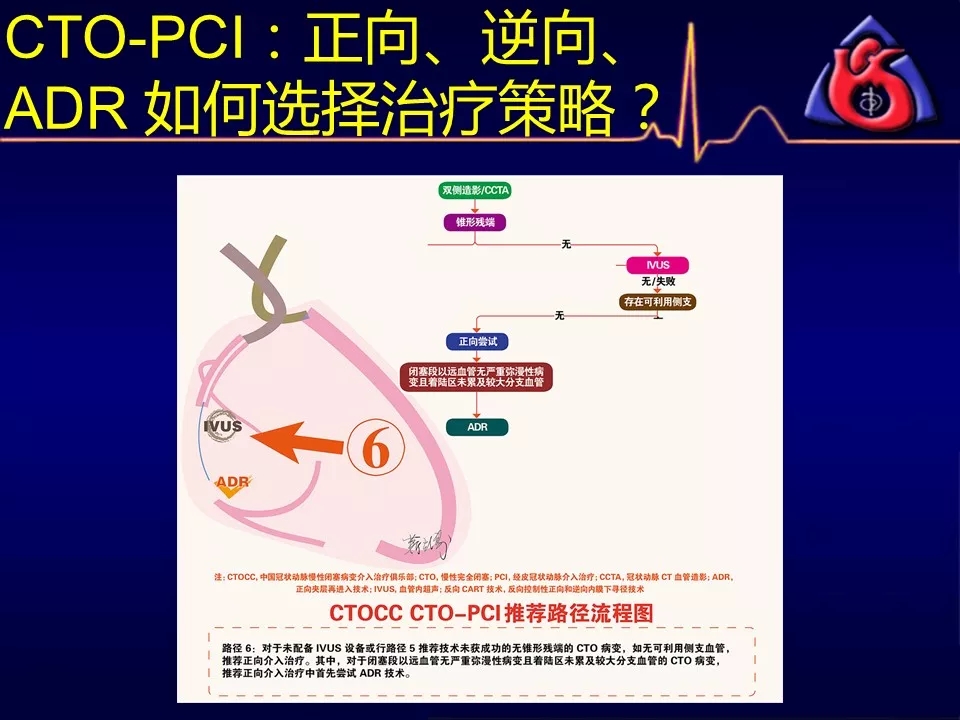

如何选择正向、逆向、IVUS指引及ADR技术?

当逆向技术困难时,如解剖条件许可,应优选ADR